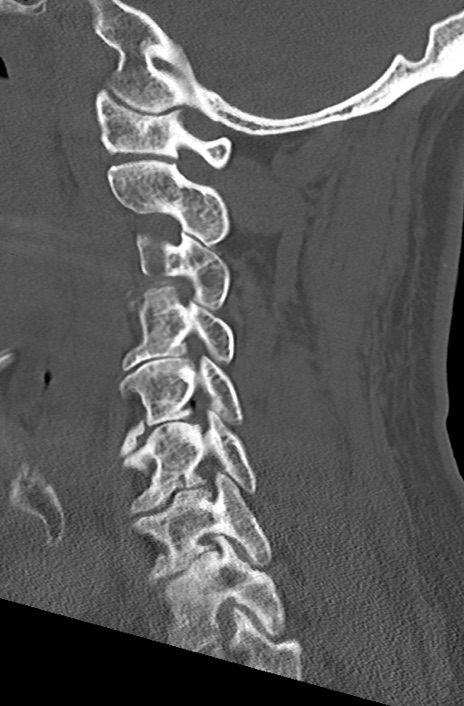

【整形】TIPS症例7 頚椎CT(矢状断像)

頚椎CT

矢状断像と横断像